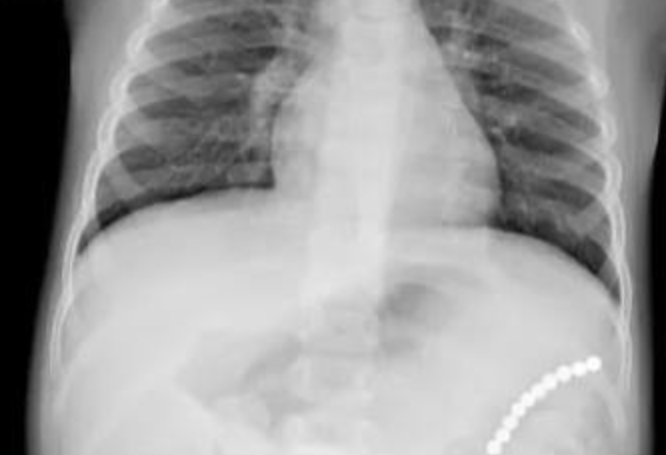

Малышка по имени Ульяна поступила в больницу из-за плохого самочувствия. Родители увидели состояние ребенка и сразу повезли ее к врачам. Первым предварительным диагнозом была пневмония, но в результате обследования выяснилось, что причина болезни в другом. Дошкольница проглотила несколько магнитов, пока родители не видели.

К счастью, родители вовремя обратили внимание на дочку и поняли, что что-то не так. Если бы прошло больше времени, малышка могла скончаться. Медики провели операцию по удалению инородных предметов, а после недолгой реабилитации ее выписали.